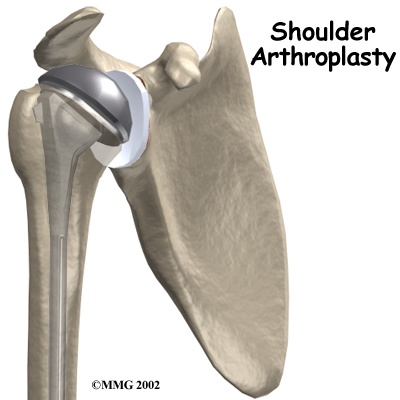

Shoulder joint replacement surgery (also called shoulder arthroplasty) can effectively ease pain from shoulder arthritis. Most people experience improved shoulder function after this surgery. Unfortunately certain patients are not candidates for a traditional joint replacement of the shoulder because they lack the muscle function necessary to stabilize the joint. A different type of shoulder replacement, called a reverse shoulder replacement, may be available for many of these patients and provide pain relief as well as a stable functioning shoulder that is adequate for their daily needs.

Shoulder joint replacement surgery (also called shoulder arthroplasty) can effectively ease pain from shoulder arthritis. Most people experience improved shoulder function after this surgery. Unfortunately certain patients are not candidates for a traditional joint replacement of the shoulder because they lack the muscle function necessary to stabilize the joint. A different type of shoulder replacement, called a reverse shoulder replacement, may be available for many of these patients and provide pain relief as well as a stable functioning shoulder that is adequate for their daily needs.

The answer to this dilemma was to rethink the mechanics of the shoulder joint and to design an artificial shoulder that worked differently than the real shoulder joint. The solution was to reverse the socket and the ball, placing the ball portion of the shoulder where the socket use to be and the socket where the ball or humeral head use to be.

This new design led to a much more stable shoulder joint that could function without a rotator cuff. The artificial joint itself provided more stability by creating a deeper socket that prevented the ball from sliding up and down as the shoulder was raised. The large deltoid muscle that covers the shoulder could be used to more effectively lift the arm, providing better function of the shoulder. The final result is a shoulder that functions better, is less painful and can last for years without loosening.

The reverse shoulder prosthesis (artificial joint) is made up of two parts. The humeral component replaces the humeral head, or the ball of the joint. The glenoid component replaces the socket of the shoulder, which is actually part of the scapula.

The reverse shoulder prosthesis (artificial joint) is made up of two parts. The humeral component replaces the humeral head, or the ball of the joint. The glenoid component replaces the socket of the shoulder, which is actually part of the scapula.

In the traditional artificial shoulder prosthesis, the glenoid prosthesis is a shallow socket made of plastic and the humeral component is a metal stem attached to a metal ball that nearly matches the anatomy of the normal shoulder. In the reverse shoulder replacement, the ball and the socket are reversed such that the ball sticks out of the shoulder itself.